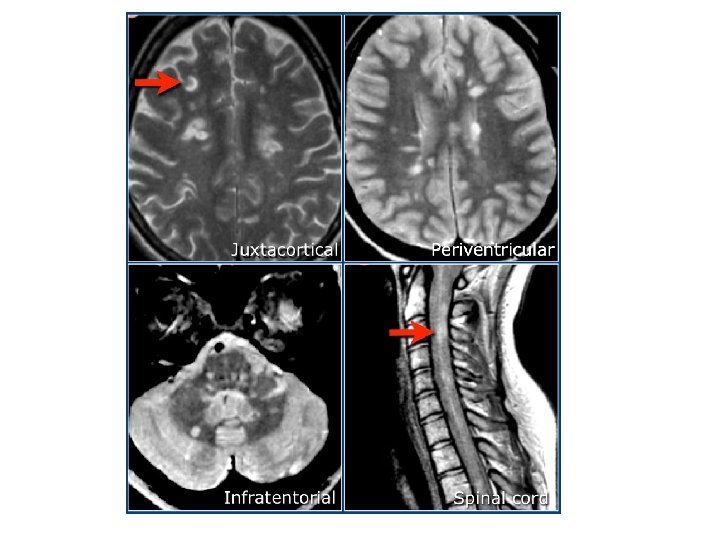

• Perivasküler inflamasyon ve demyelinizasyon • SSS’de plaklar – En sık: optik sinir, periventriküler ak madde, beyin sapı, serebellum, spinal kord • Primer olarak aksonlar etkilenmez

MRI BULGULARI • Periventriküler ak maddede plaklar • Serebellum / beyinsapı / servikal ve torakal spinal kord • Kontrast madde (Gadolinium) tutulumu aktif lezyon varlığını gösterir – Her zaman hastalık aktivitesinde artış ile korelasyon göstermez

MRI • MRI anormalliği: – Kesin MS’de %90 – Olası MS’de % 70

SEREBELLUMDA PLAKLAR

OPTİK SİNİR TUTULUMU

AK MADDE LEZYONLARI